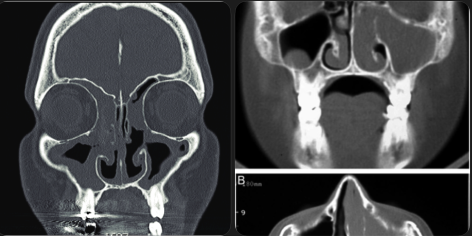

2. CT Scan of the Sinuses (if needed)

CT helps assess:

- Severity

- Sinus involvement

- Surgical planning if required

Diagnosis is mainly clinical + endoscopic.